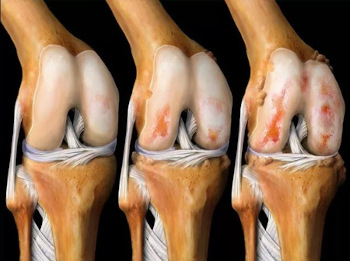

Utjecaj artroze na hrskavično tkivo koljenskog zgloba.